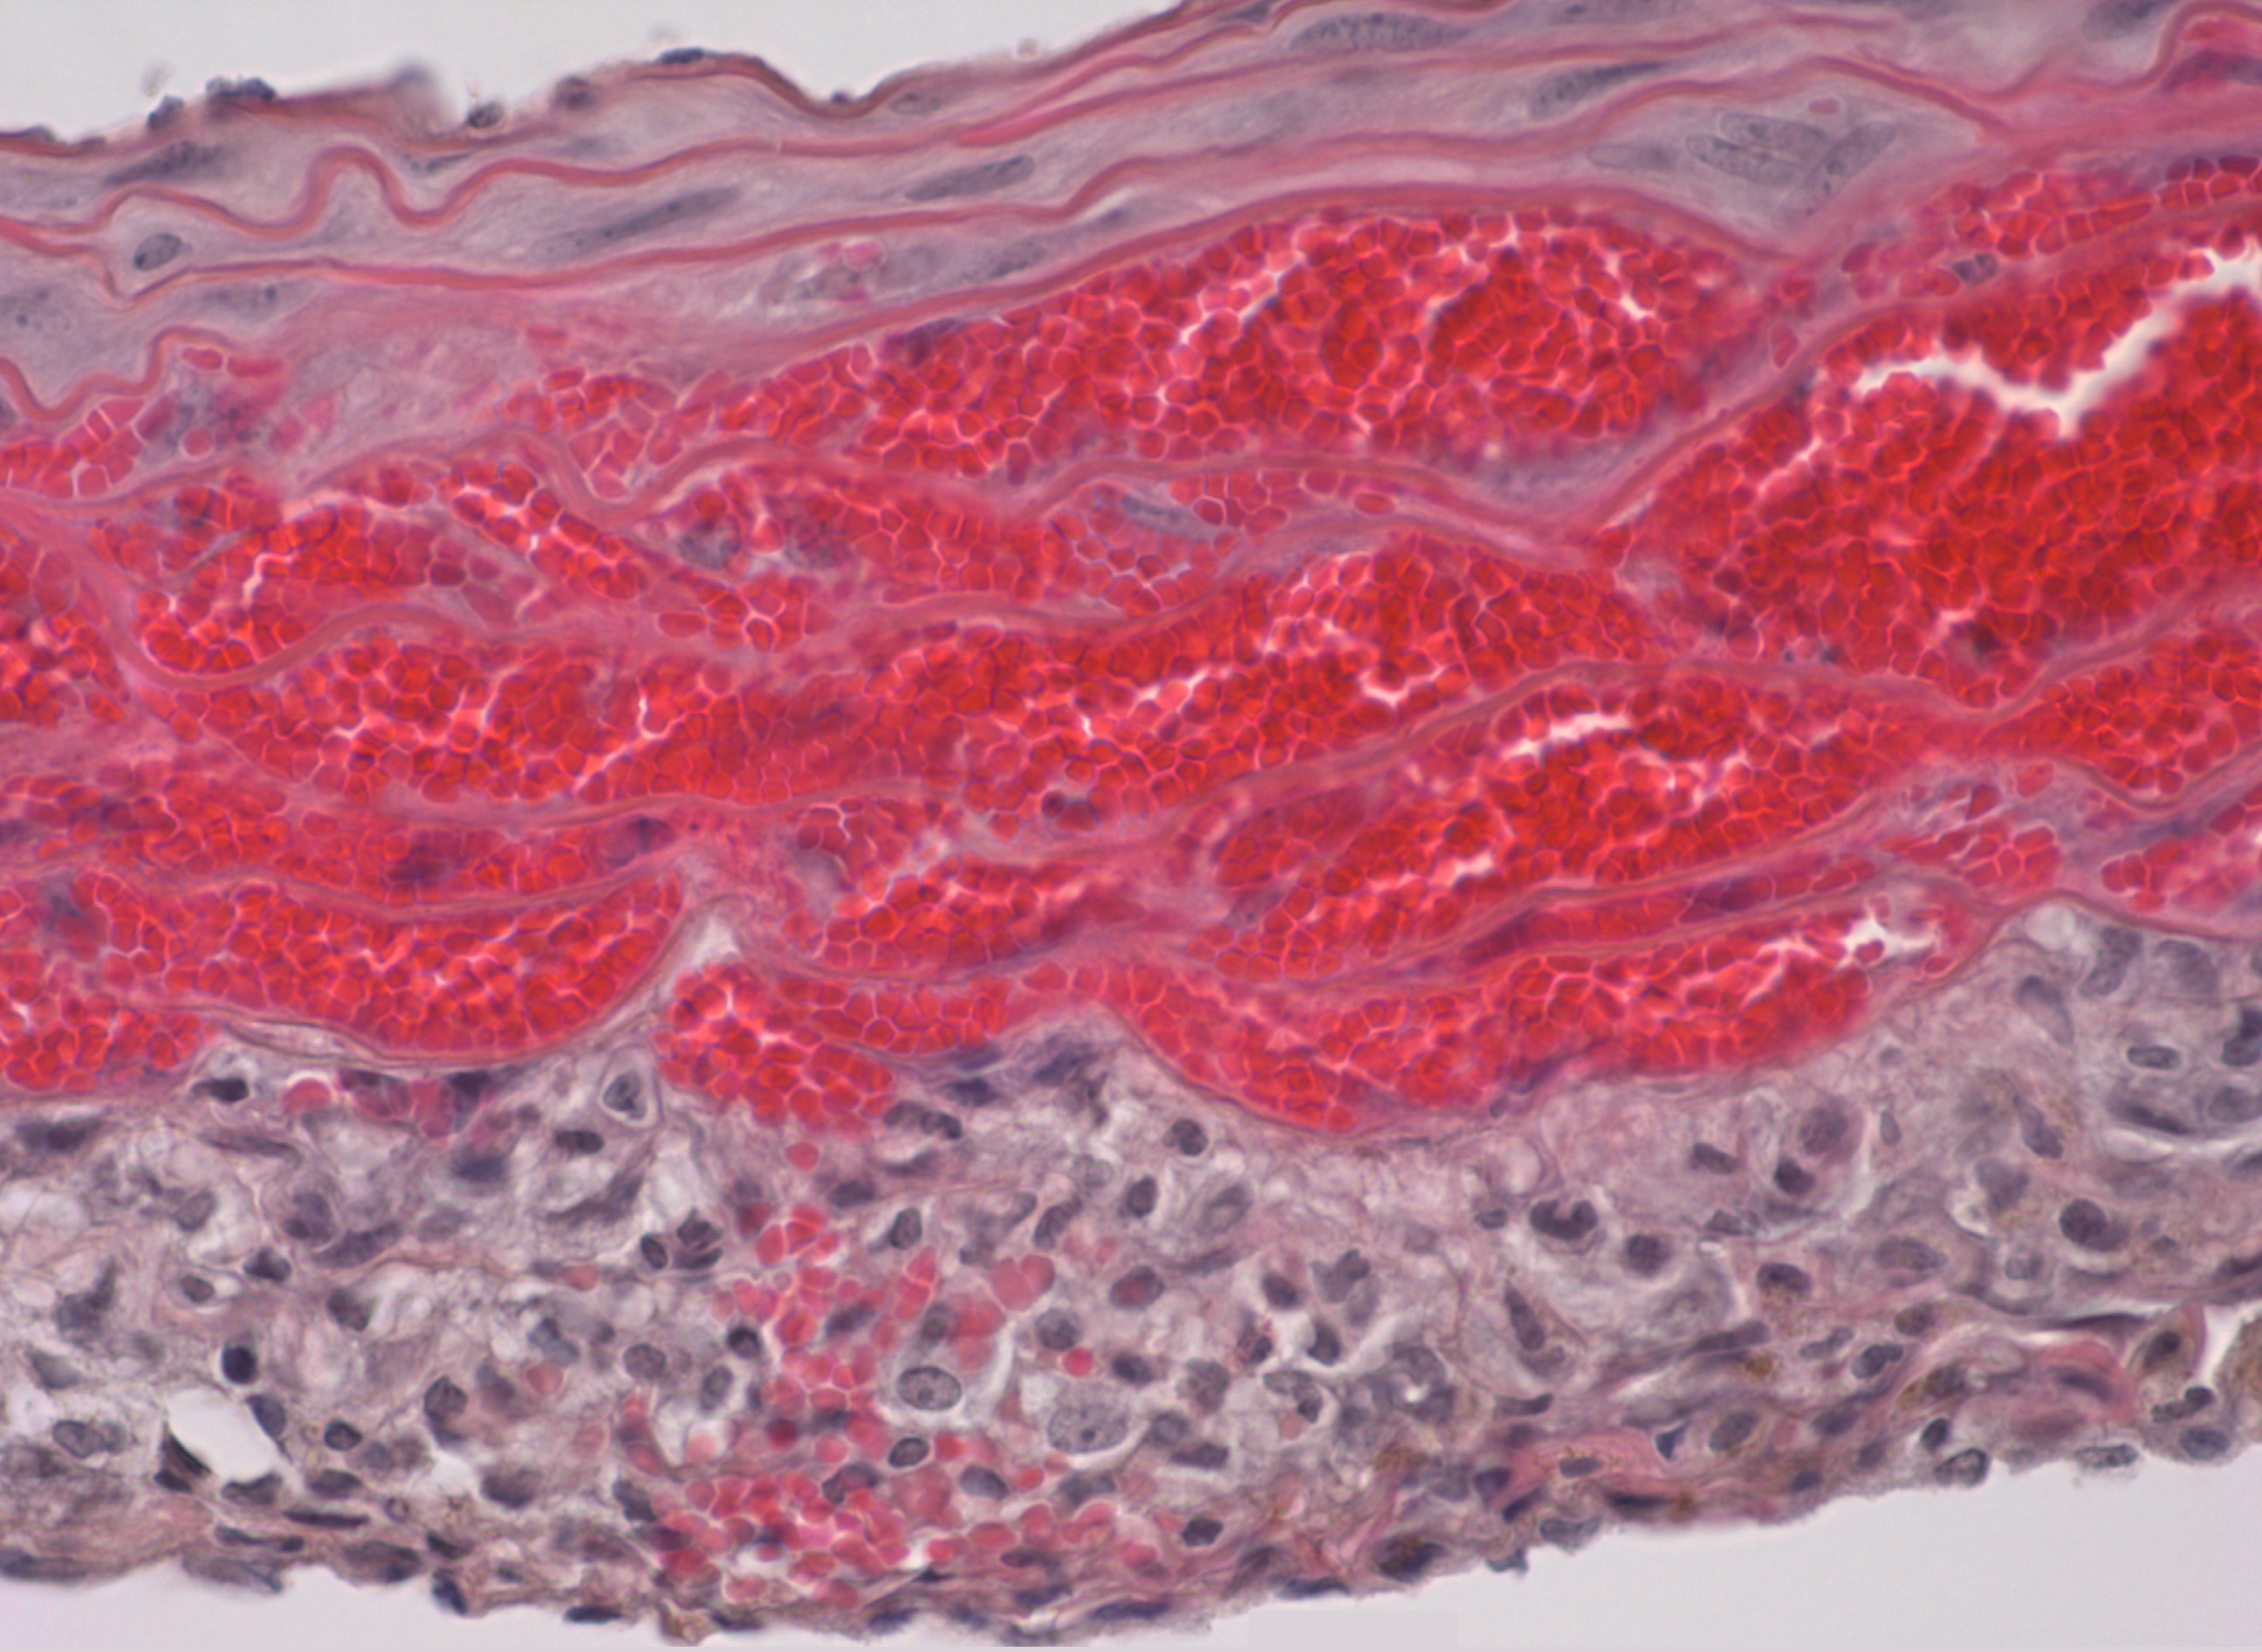

El hematoma intramural consiste en una acumulación de sangre dentro de la pared de la aorta sin disección (desgarro) de su capa íntima (la capa más interna, en contacto con el torrente circulatorio). En los pacientes afectos, el hematoma intramural puede, en su fase aguda, reabsorberse espontáneamente o evolucionar con rapidez a disección aórtica en su fase aguda, explican los investigadores. Por otro lado, la evolución más común a largo plazo de esta enfermedad conduce hacia el desarrollo de un aneurisma, es decir, una dilatación o ensanchamiento anómalo de una porción de la aorta, que también puede provocar su rotura y, por lo tanto, la muerte del paciente.

Los investigadores han generado un modelo animal que reproduce con un alto grado de fidelidad muchas de las características de la enfermedad humana y que ha permitido profundizar en los mecanismos moleculares involucrados en la formación y evolución del hematoma intramural. De esta forma, han descubierto que la presión arterial elevada es un detonante de esta patología. El Dr. Campanero explica: “Hemos descubierto que los ratones en los que inducimos la deficiencia de la proteína Rcan1 en edad adulta son extraordinariamente sensibles a la formación del hematoma intramural en la arteria aorta y a su posterior rotura en respuesta a diversos estímulos que aumentan la presión arterial”. Por otra parte, añade el Dr. Redondo, “nuestro estudio muestra que diversos fármacos usados habitualmente para reducir la presión arterial en humanos y en ratones previenen completamente la formación del hematoma intramural en el modelo preclínico que hemos generado”.

Los investigadores han analizado también los mecanismos moleculares involucrados en la formación del hematoma intramural. Así, los resultados de la investigación demuestran que al inducir la deficiencia de Rcan1 en las células de la pared vascular se activa la proteína MLC (cadena ligera de miosina), la cual está implicada en la constricción de los vasos. El estudio, aseguran, muestra que “la inhibición farmacológica de la activación de MLC previene eficientemente la formación del hematoma intramural”.